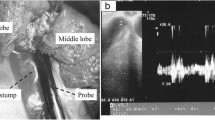

A 68-year-old man (height: 169 cm, weight: 68 kg) who was receiving medical treatment for hypertension and diabetes mellitus was diagnosed with stage 1B adenocarcinoma of the lung based on the findings of investigations including computed tomography (CT) after an abnormal shadow was noted in his left upper lung field on a chest radiograph during a medical checkup. He was scheduled for left upper lobectomy via VATS. Surgery was performed under general anesthesia with thoracic epidural analgesia in the right lateral recumbent position. Before induction of general anesthesia, a thoracic epidural catheter was placed in Th4/5, induction was done with propofol and remifentanil, muscle relaxation was obtained with rocuronium, and double-lumen tube was intubated endotracheally to maintain anesthesia with intermittent lidocaine administration into the epidural space and desflurane inhalation. On the first postoperative day, the patient started eating and getting out of bed, but atrial fibrillation with a heart rate of 120–150 beats/min appeared. A transdermal patch of bisoprolol 4 mg/day was applied, and the heart rate was maintained at 80–100 beats/min. Patient-controlled epidural analgesia provided good pain control with the Prince Henry Hospital pain scale is less than or equal to 2 and was used until the 4th postoperative day. Although atrial fibrillation persisted, the heart rate was controlled well with bisoprolol, and there were no other complications; therefore, the patient was discharged on the 5th postoperative day. On the 7th postoperative day, the patient experienced light-headedness and dyspnea while walking to the bathroom, but the symptoms quickly improved. On the 8th postoperative day, the patient experienced dyspnea and visited our hospital. Contrast-enhanced CT revealed a thrombus (18 mm in diameter) attached to the resected edge of the left pulmonary vein (Fig. 1), although no pulmonary edema was observed, blood flow in the pulmonary veins was greatly impeded. The patient was immediately readmitted to the hospital, and an echocardiogram was obtained, which showed no evidence of right heart overload, heart failure, or hypoxemia. Heparin 18,000 units/day was immediately started. However, the activated partial thromboplastin time did not prolong, even after the dose was increased to 25,000 units/day. Therefore, the patient was switched to 60 mg of edoxaban tosilate hydrate. Sinus rhythm was achieved on the 10th postoperative day, and the patient was discharged on the 24th postoperative day because the thrombus was shrinking, and no dyspnea was observed. The thrombus was confirmed to have disappeared on the 66th postoperative day.